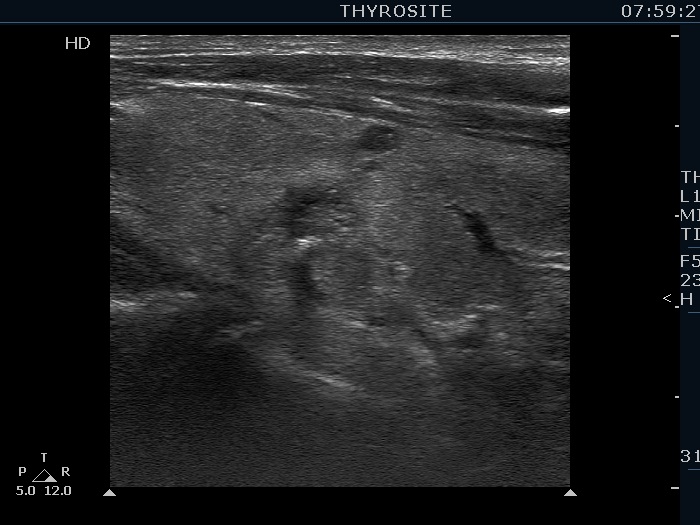

Benign colloid goiter (cytological diagnosis)

This nodule presents different types of hyperechogenic granules, the ventral figures are either comet-tail artifacts or punctate echogenic foci, while although the primary focus cannot be seen, the acoustic shadows prove that there are coarse calcifications, as well.